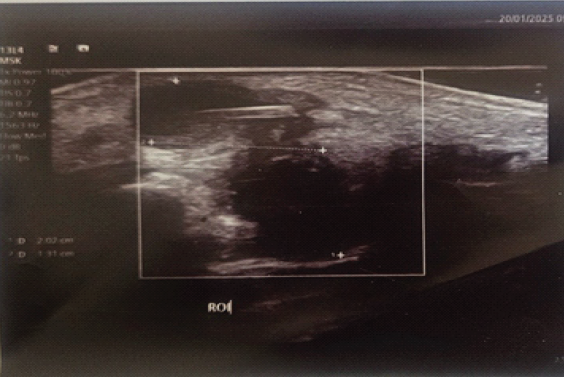

On ultrasonography of the hand of the hand an elongated linear hyperechoic foreign structure measuring 1.07 cm long lying within a cystic collection that measured 2.02 cm × 1.31 cm with no vascularity changes (Fig. 3). Hematological studies were all within normal limits except anemia of hemoglobin = 10.1 of note C-reactive protein was normal.

Figure 3: Ultrasonography of the hand of the hand an elongated linear hyperechoic foreign structure measuring 1.07 cm long lying within a cystic collection that measured 2.02 cm × 1.31 cm with no vascularity changes.